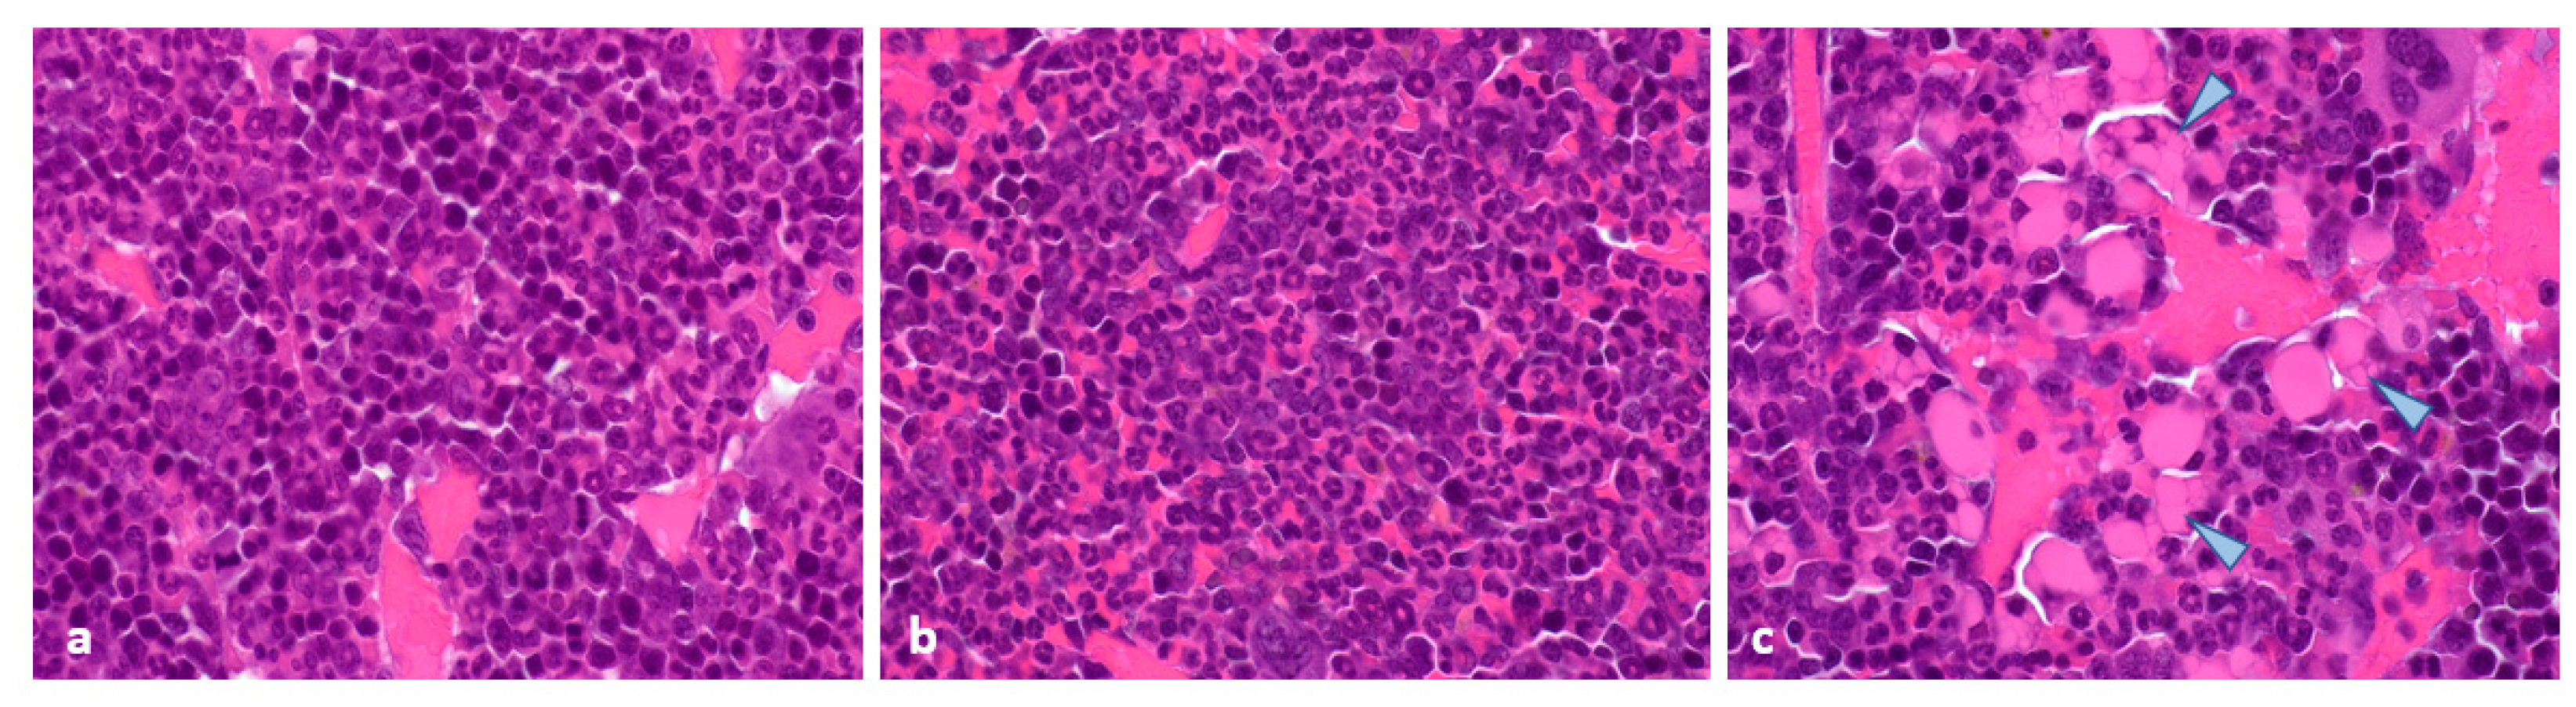

Compared to controls (Figure 4a), histopathological examination of tumours at 96 h after the fourth injection of the test substances showed a complete loss of mitoses following treatment with [177Lu]Lu-satoreotide tetraxetan at 15 MBq and [177Lu]Lu-DOTA-TATE at 30 MBq (Figure 4b). There was an important decrease in mitotic counts following treatment with [177Lu]Lu-DOTA-TATE at 15 MBq, although evidence of mitotic activity remained (Figure 4c). The presence of degenerating cancer cells with a vacuolated cytoplasm and/or accumulation of granular eosinophilic material was also noted (Figure 4b, arrowheads). Sirius red staining revealed slightly higher fibrosis in the [177Lu]Lu-satoreotide tetraxetan-treated tumours (Figure 4e) compared to the vehicle control tumours and [177Lu]Lu-DOTA-TATE-treated tumours (Figure 4d,f). In line with the higher tumour radioactivity uptake of [177Lu]Lu-satoreotide tetraxetan at 15 MBq as compared to [177Lu]Lu-DOTA-TATE at 15 or 30 MBq, [177Lu]Lu-satoreotide tetraxetan produced more DSBs than [177Lu]Lu-DOTA-TATE treatments, as reflected by a higher mean pH2AX H-score (Figure 4g–i).

Figure 4. Histopathological and immunohistochemical analyses at 96 h post-administration of last treatment. (a,b) are representative images of haematoxylin and eosin (H&E) tumour staining. (a) The arrowheads point to mitoses in a control/untreated tumour. (b) In a [177Lu]Lu-satoreotide tetraxetan-treated tumour, mitoses were absent. The arrowheads point to degenerating cells. (c) Mean ± standard error of the mean (SEM) mitotic count (ranging from 22 to 66 at objective 40 in control tumours). (d,e) are representative images of sirius red staining. (d) In a control/untreated tumour, fibrosis was absent. (e) Fibrosis grade 1 (minimal) was noted in a [177Lu]Lu-satoreotide tetraxetan-treated tumour. (f) Mean ± SEM fibrosis score, ranging from 0 to 4. (g,h) are representative images of pH2AX tumour staining. (g) In a control/untreated tumour, there were low levels of staining in the nuclei of cancer cells (arrowheads) unlike in a [177Lu]Lu-satoreotide tetraxetan-treated tumour (h). (i) Mean ± SEM pH2AX H-score, ranging from 0 to 300. Figure (a,b,d,e) were taken at the objective 40, and figures (g,h) at the objective 100.